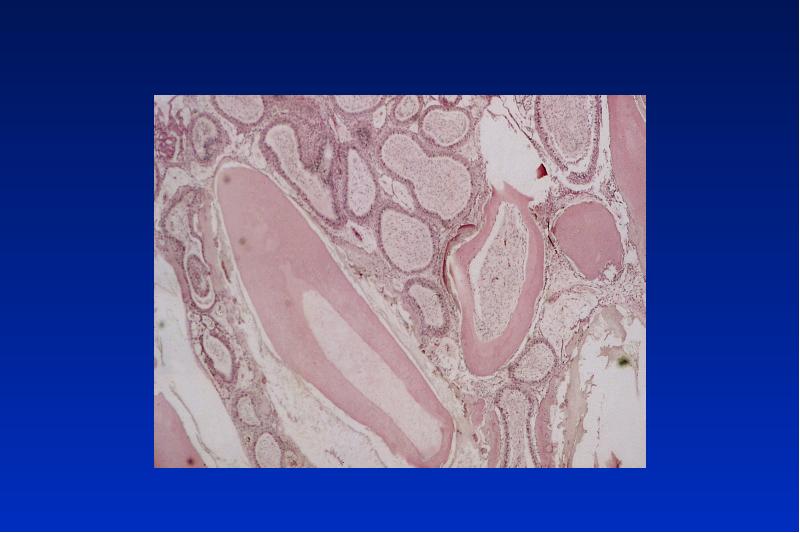

- 13. Follikuläre Zyste Ät: dysontogenetische Zyste Lok: OK- Caninusregion, UK- 3 Molar

- 17. Eruptionszyste Sonderform einer follikulären Zyste umgibt die Zahnkrone eines durchbrechenden Zahnes